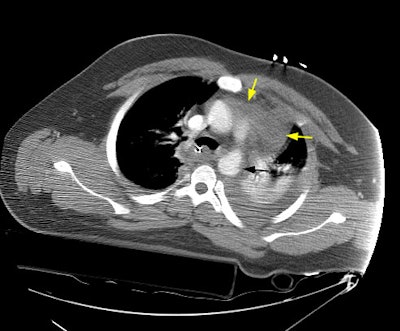

A CT scan of the chest demonstrated a large mediastinal hematoma (yellow arrows) and a left pleural fluid collection that was subsequently found to be a hemothorax. There was irregularity to the aortic arch near the isthmus (black arrow) which is highly suspicious for an aortic laceration, however, images at the level of the diaphragmatic hiatus demonstrated a more impressive finding (below).